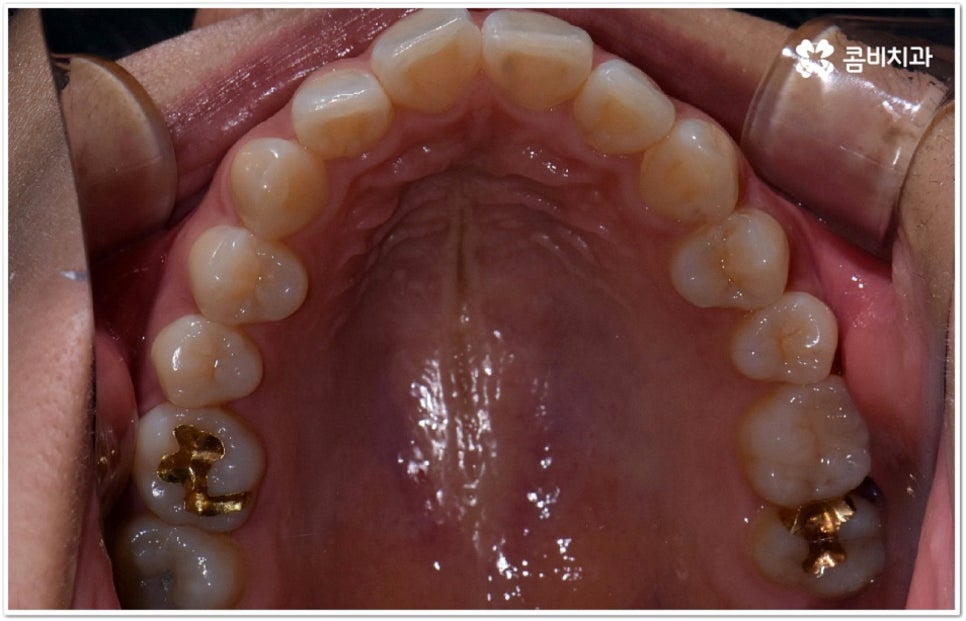

현재는 크게 불편함이 없고 환자분들의 입장에서 볼 때 스스로 교정이 딱히 필요하다고 생각되지 않는다고 해도 정밀 검진을 받아보는 것이 도움이 되는 또 다른 이유는 덧니가 생긴 원인, 구조적인 부분 등을 꼼꼼하게 체크해 봤을 때 혹시라도 추후에 치열이 더 많이 삐뚤어지거나 턱관절에 좋지 않은 영향을 줄 수 있는 상황이라면 미리 대처할 수 있다는 데 있어요. 본을 떠 보고 3D CT 를 이용해 겉으로 보이지 않는 부분까지 함께 살펴보면서 악궁 및 치아의 크기와 각도, 상악과 하악의 발달 정도 등 각자의 상황을 종합적으로 분석해 보면 앞으로의 이동 방향이나 정도 등을 어느 정도 예측해 볼 수 있는데요. 가능하다면 문제가 커진 다음에 바로잡는 것보다 지속적인 관찰을 통해 적절한 시기에 필요한 치료를 하는 것이 시간과 노력을 덜 들이는 방법이 될 거예요.

덧니의 원인에는 여러 가지가 있는데 대표적으로는 유치가 너무 일찍 빠져서 영구치가 제대로 자리를 잡지 못했거나 턱뼈의 크기와 치아 크기가 조화를 이루지 못하는 경우 등 공간이 부족한 상황을 생각해 볼 수 있어요. 덧니는 주로 송곳니가 가장 흔하나, 치열이 공간이 부족할 경우 이론적으로는 어떤 치아라도 덧니가 될 수 있어요. 이때 원인과 정도를 꼼꼼하게 파악하여 만약 해당 부위만 부분 교정이 가능하다면 덧니부분교정 치료를 할 수 있는데요. 덧니부분교정 을 이용하면 원하는 부위에만 브라켓을 부착하여 치아 이동을 시키기 때문에 전체 교정에 비해서 간편하며 치료 기간도 6~8개월 정도로 줄어들고 통증도 많이 감소될 수 있습니다. 비용적인 부담도 덜하며 (삐뚤어진 정도나 상태에 따라 다르겠지만) 보통 덧니부분교정 의 경우 비발치 과정으로 진행되기 때문에 환자분들의 입장에서는 덧니부분교정 을 많이 선호하시는 편이라고 할 수 있어요. 상황에 따라 미니스크류, 치간삭제, 악궁확장장치 등 환자에게 맞는 비발치 방법을 이용하여 도움 받을 수 있습니다.

하지만 모두에게 덧니부분교정 을 적용할 수 있는 것은 아니므로 먼저 3D CT와 같은 정밀 검사 장비를 통해서 턱의 구조적 특성 및 치열과 교합 등 구강 내부 상황에 대해 세세하게 검진을 하고 충분한 상담을 통해 각자에게 적합한 계획을 세운 다음 무리하지 않게 치료를 진행할 필요가 있어요. 만약 부분 교정을 진행할 수 없다고 해도 교정 장치를 이용하여 기간이나 통증 부분의 부담을 덜 수 있으니 너무 실망하실 필요는 없을 거예요.